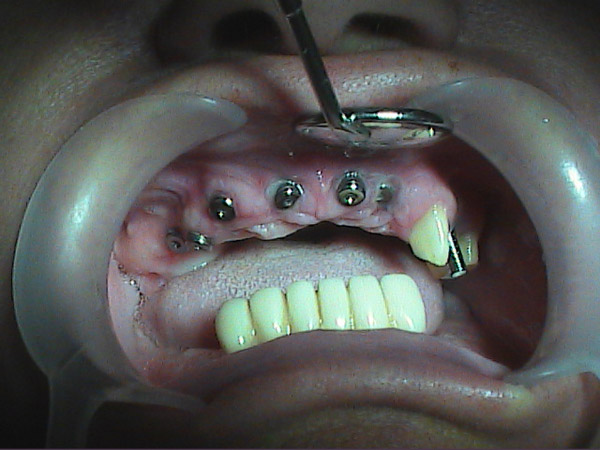

"Je suis très content des soins qui m'ont été prodigués par le Dr Manu et je ne peux que vous le conseiller fortement. Moi j'ai pay pour chaque implant 550 Euros et 190 Euros par couronne du porcelaine sur métal qui on été fait par des prothésistes qui sont à 2mn en voiture du cabinet du centre ville (Il en a deux et selon les soins vous allez à l'un ou à l'autre) et souvent il m'a prodigué des soins gracieusement. En france ou autour on aurait multiplié la facture par 2 au moins."